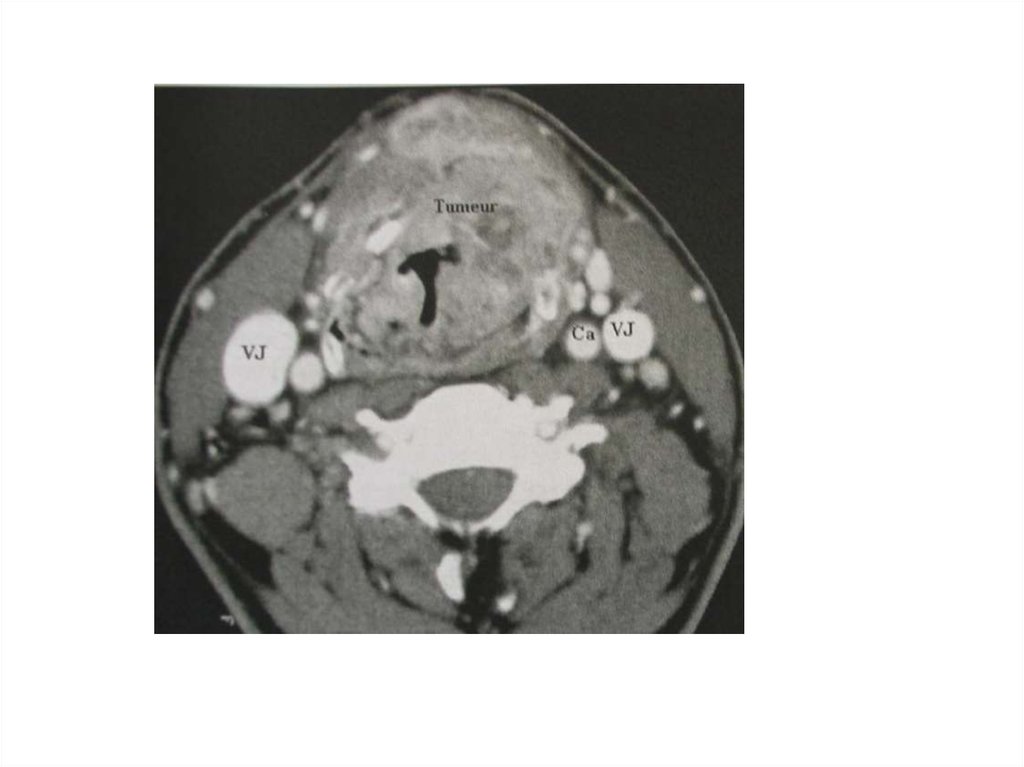

17. Примеры патологии

1. Пациент И., 18 лет

• Диагноз: Острый стенозирующий ларинготрахеит.

Стеноз гортани 3 степени.

• An. morbi: заболел остро, болен в течении 2-х

дней, заболевание началось с кашля и

температуры . Дома принимал парацетамол

полоскал горло, но состояние не улучшилось. На

3-ый день заболевания, когда появились лающий

кашель, осиплость голоса, затруднение дыхания,

повышение температуры тела, обратились в ГКБ.